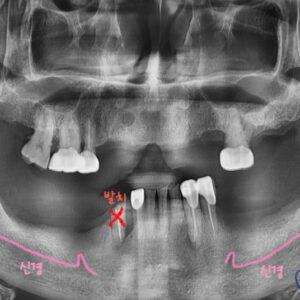

저희 치과에 내원해 주신 환자분의 구강 내 모습입니다

오래전 왼쪽 위 다수 치아를 발치 하셨습니다.

그로 인해 식사 시 한쪽으로만 저작을 하여 불편감이 많아

그 점을 해결하고자 내원해 주셨습니다